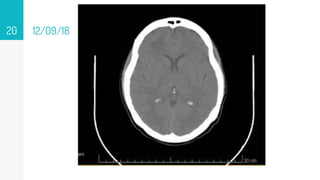

12/09/18

▹ 12/09/18

Pegar tc

La TC tiene sensibilidad de 95 a 99%, pero con una especificidad sólo de 80 a 85%, la cual disminuye a